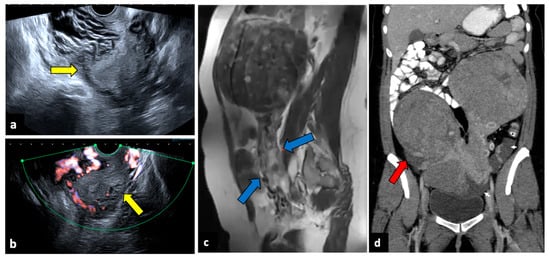

Ectopic pregnancy (EP) is the implantation of a fertilised ovum outside the uterine cavity and, due to the risk of massive bleeding, is a potentially life-threatening gynaecological emergency, representing the leading cause of maternal mortality in the first trimester, with an incidence of 5–10% of all pregnancy-related deaths [74,75]. Predisposing risk factors are a previous EP, tubal ligation, a copper intrauterine device (IUD), and artificial insemination. EP most often occurs along the fallopian tubes (97%), especially close to the ampulla. Still, it can only occur in the cervix (Figure 11), in the ovaries, along a previous Caesarean scar, or within the abdominal cavity [76]. EP rupture with massive intra-abdominal bleeding often occurs after 10 to 14 weeks of gestation. A sign of a rupture is severe APP with vaginal bleeding and even haemorrhagic shock. Due to the risk of life-threatening haemorrhages, an early diagnosis of this condition is pivotal. In addition to the pregnancy test, both transabdominal and transvaginal US are essential and show an empty uterine cavity with decidualised endometrium (“decidual sac sign”). The ovarian region should be closely evaluated since a complex extra-adnexal cyst/mass or dilatated tubes are frequently detected in a tubal EP. Usually, a large amount of free peritoneal fluid and/or haemoperitoneum is also observed. The gestational sac appears during the US examination as a ring-shaped lesion with an anechoic centre and a broad, hyperechoic, hypervascular rim (tubal ring sign) [77]. However, in several cases, US cannot definitively exclude EP, and MRI may be helpful by providing a larger field of view and more accurate anatomic localisation. Peri-adnexal masses, haematosalpinx, and haemoperitoneum are the most frequent MRI findings [78,79,80].

Figure 11.

Ruptured cervical ectopic pregnancy in a thirty-three-year-old patient who presented at the emergency department with acute pelvic pain and severe vaginal bleeding. MRI sagittal (a) and axial (b) T2-weighted, and sagittal T1-weighted early contrast-enhanced fat-saturated (c) images show an empty uterine cavity and a ruptured ectopic pregnancy within the cervical canal (yellow arrows). This patient was managed with uterine arteries embolisation. Preprocedural images (d) show a hypervascular area in the region of the cervical ectopic pregnancy that is supplied mainly by the right uterine artery. Post-embolisation (e) arteriogram demonstrates complete stasis.